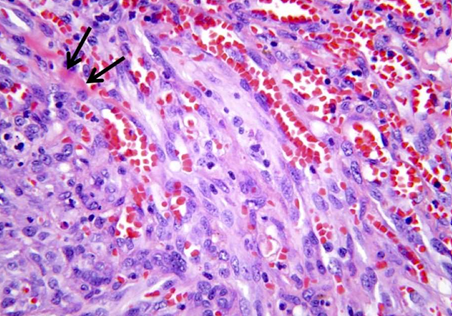

IHD: Myocardial infarction

Acute Myocardial Infarction

2-3 ds: Coagulative necrosis, Dense neutrophilic infiltrate in an area of acute myocardial infarction